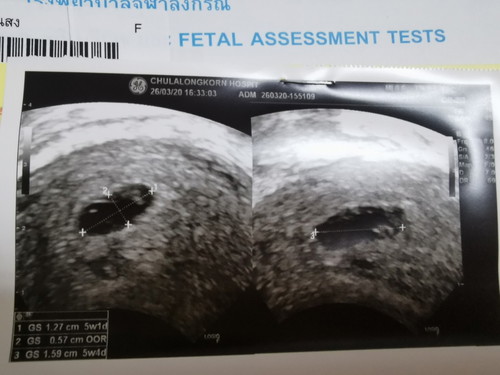

สอบถามค่ะ อัลตร้าซาวด์ครั้งแรกหมอบอกอายุครรภ์ประมาณ5วีค เจอถุงการตั้งครรภ์แต่ยังไม่เจอเจ้าตัวเล็ก หมอนัดซาวด์ใหม่อีก2สัปดาห์ แบบนี้ยังมีความหวังไหมคะ?

ใจเย็น ๆ นะคะ บ้านนี้เห็นตัวน้องตอน 8w ค่ะ ☺️